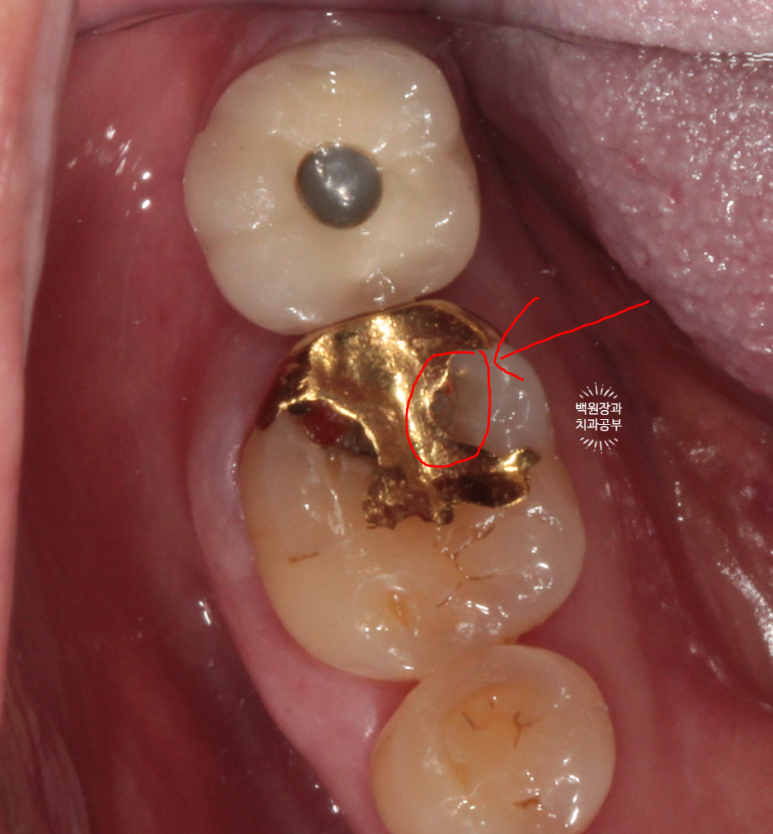

그림판으로 그리니 뭔가 더 쉬운데요? ㅎㅎ

빨간색으로 보이는 것은 음식물입니다.

오래 전에 붙여놓은 골드 인레이 주변으로 2차 치아우식증 (2차 충치)가 발생하여 그 틈으로 접착제가 녹아 골드인레이가 떨어진 것이었어요.

저 골드인레이를 제거하면 하방에 분명한 2차 충치가 있습니다.!!!